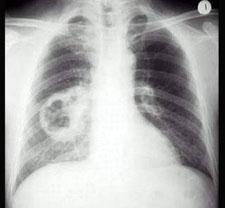

问题 男,54岁,咳嗽,伴胸痛两周,午后有低热,出汗较以前增多,胸片如图,最可能的诊断是 ( )

选项 A、肺癌 B、肺大疱 C、结核空洞 D、韦格氏肉芽肿 E、肺脓肿

答案 A